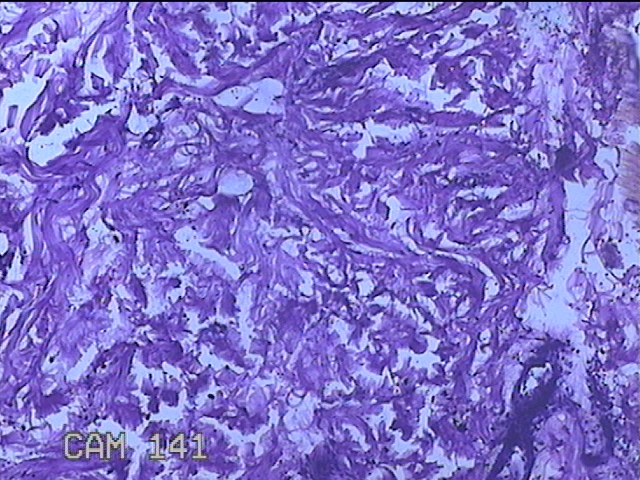

左侧臀部结节

性别

男

年龄

40岁

临床诊断

皮下结节

一般病史

发现左侧臀部结节1年余。

标本名称

大体所见

灰白粉红色组织1.3x0.8x0.3cm一块,表面带梭形皮肤1.3x0.8cm,皮下见结节1.3x1x0.7cm一个,切开结节呈实性,切面灰白粉红色,质软。